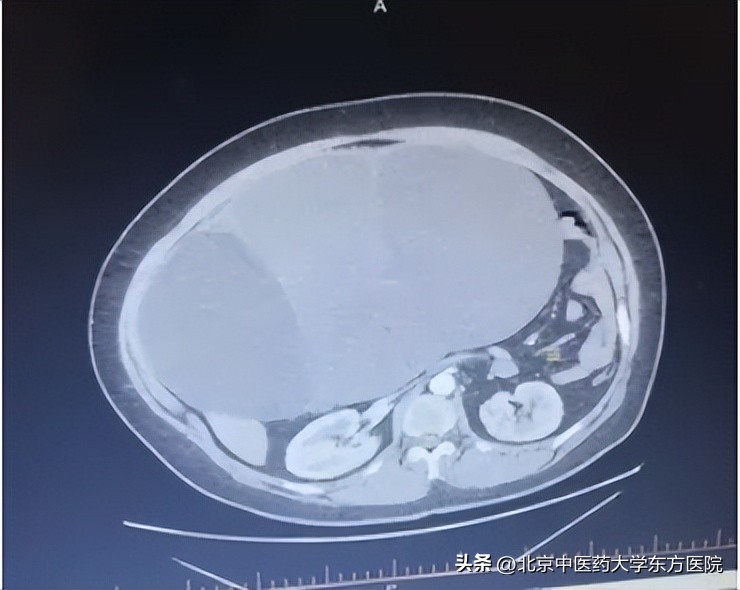

33岁李女士,结婚10余年未怀孕,近半年腹部逐渐增大,家人以为怀孕,甚是欢喜。然而患者月经却又每月来潮,饮食睡眠均无异常。近3月来偶有爬楼后轻度喘气,就诊于当地医院,盆腔CT提示腹腔内多发囊性占位,大小约33×21×26cm,考虑卵巢囊腺瘤,为求手术治疗,就诊于东方医院。

入院查体见:患者形体偏胖,腹部膨隆,如孕足月大小,腹壁张力较高。专科检查:子宫前位,大小正常,活动可,盆腔可及肿物如足月大小,上至剑突下三指,质中,无明显压痛。入院CT及核磁检查考虑卵巢囊腺瘤,来源于右侧附件可能。